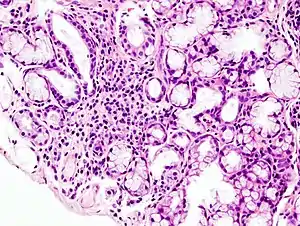

| Image with a microscope of focal lymphoid infiltration in the minor salivary gland associated with Sjögren's syndrome. | |